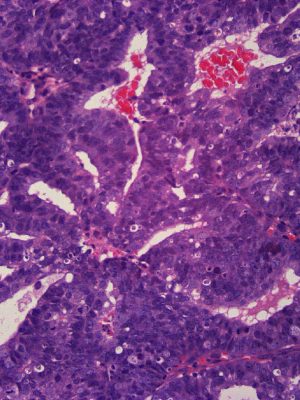

Gynecologic & Breast Pathology

Dr. Ramdall has specialized expertise in the diagnosis of various gynecological and breast disorders, including:

• Benign and malignant neoplasms

• Immunohistochemical staining for ER/PR/HER2

• Reflex HER2 FISH (Fluorescence in Situ hybridization) testing as indicated